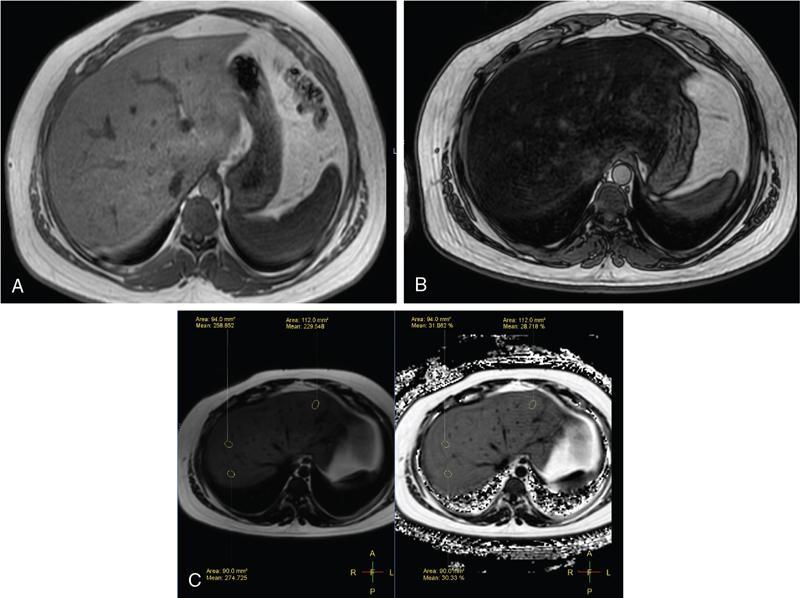

Excessive triglyceride accumulation within hepatocytes is defined as hepatic steatosis. Major conditions associated with hepatic steatosis include alcoholic fatty liver disease (AFLD) and nonalcoholic fatty liver disease (NAFLD). Causes of hepatic steatosis are discussed in Table 9.10.3. NAFLD is the most common form of hepatic steatosis and discussed in detail below. Up to 90% of patients with chronic alcoholic intake have fatty liver. Those with pure AFLD have a 10% risk of progressing to cirrhosis. Consumption of 30 g ethanol/day shows increased risk of chronic liver disease and cirrhosis. Other risk factors include female sex, obesity, cigarette smoking, obesity and associated risk factors. These factors are divided into 2 main categories which can cause fatty liver: inborn errors of metabolism and acquired metabolic disorders. Inborn errors of metabolism include abetalipoproteinemia, galactosemia, glycogen storage disease, hereditary fructose intolerance, homocystinuria and Wilson disease. Inflammatory bowel disease, jejunoileal bypass, malnutrition, starvation and total parenteral nutrition are acquired metabolic factors associated with increased risk. Chronic HCV infection, is associated with hepatic steatosis, with prevalence of 40%–80%. Hepatic steatosis can be seen as an adverse reaction to some medications such as tetracycline, valproic acid, some of chemotherapeutic agents, dexamethasone, amiodarone, methotrexate, tamoxifen and acetylsalicylic acid. Either microvesicular or macrovesicular steatosis can be observed in drug-induced hepatic steatosis. It generally occurs with therapy lasting several weeks or months and is reversible after discontinuation. The leading cause of hepatic steatosis in paediatric population is NAFLD. Six per cent of these patients develop cirrhosis and end-stage disease. Other less common causes include starvation and malnutrition, drugs (glucocorticoids, oestrogens, tetracyclines, and methotrexate), intoxications (carbon tetrachloride, organic phosphates, organic solvents, and alcohol), metabolic disorders, hepatitis C infection, and total parenteral nutrition. NAFLD is defined as steatosis affecting >5% of hepatocytes in the absence of a secondary cause. NAFLD represents a spectrum of disease, ranging from simple steatosis to steatohepatitis through to fibrosis and cirrhosis and in some cases hepatocellular carcinoma. NAFLD is a growing epidemic worldwide in part due to obesity and insulin resistance leading to liver accumulation of triglycerides and free fatty acids. Nonalcoholic steatohepatitis (NASH) is defined by histologic terms as a necroinflammatory process whereby the liver cells become injured in a background of steatosis. 20% of patients with NAFL progress to NASH, which progresses to fibrosis and cirrhosis over a 15-year time period (Fig. 9.10.3). The definition of NAFLD requires imaging or histology evidence of steatosis and no causes for secondary hepatic fat accumulation like significant alcohol intake, drugs or hereditary disorders (Table 9.10.4). The incidence of NAFLD ranges from 20% to 30% in Western countries and 5%–18% in Asia. As it currently stands, NAFLD represents the second most common reason to be listed for a liver transplant. The prevalence of NAFLD is higher in patients with obesity, diabetes, and patients with hyperlipidaemia. Prevalence increase with age from less than 20% at age 20 to more than 40% over 60 years of age. Males show a higher risk for progression to NASH and fibrosis (Table 9.10.5). Up to 90% of patients with NAFLD have simple steatosis, and about 30% of patients with NAFL develop NASH, and in again about 30%–40% of NASH patients the disease progresses to manifest fibrosis and cirrhosis NAFLD related cirrhosis has a 10-year mortality of 25% and a 5% chance of developing end-stage liver disease and HCC. The theory implicated in the pathogenesis of NAFLD is the two-hit theory. Insulin resistance, enhanced dietary influx and increased hepatic lipogenesis leading to accumulation of triglycerides (TG) and FFA in the hepatocytes is the first hit. The lipid peroxidation, mitochondrial dysfunction and inflammation resulting in hepatocyte damage and development of liver fibrosis is the second hit. The stages of NAFLD on histology range from steatosis initially to hepatic fibrosis in late stages. In the steatotic stage large (macro-) and small (micro-) vesicles of fat, predominately triglycerides, accumulate within hepatocytes. The affected parenchyma is divided into thirds: 5%–33%, 34%–66% and >66% and graded as mild, moderate and respectively. Ballooned hepatocytes with accompanied steatosis and inflammation are characteristic of the steatohepatitis stage. Fibrosis has a characteristic appearance with early lesions showing a perisinusoidal deposition followed by periportal fibrosis which progresses to bridging. Raised GGT is the most common liver enzyme elevated in NAFLD. Transaminases are within normal range in 80% patients. No specific blood tests can diagnose NAFLD. Liver biopsy has remained the gold standard for diagnosis and quantification of liver fat. Drawbacks, however, include invasive nature, sampling error and procedure related complications like bleeding. Various imaging techniques are currently available in diagnosing and quantifying liver fat. MRI in particular proton density imaging and MR Spectroscopy have revolutionized imaging of fatty liver. Normal liver parenchyma is the same as or slightly more echogenic than the adjacent kidney and spleen. Fat deposition leads to increased echogenicity of liver. Decreased beam attenuation in patients with fatty change leads to poor visualization of structures such as intrahepatic vessels, bile ducts and liver lesions and in severe cases diaphragm (Table 9.10.6). Fatty liver can be graded on USG as: US has a fair accuracy of detecting the moderate to severe hepatic steatosis with sensitivity of about 90% and specificity of about 95% for patients without concomitant chronic liver disease. Ultrasound is observer and equipment dependent. Confounding factors such as large body hiatus may lead to overestimation of hepatic steatosis due to beam attenuation by overlying fat. Conditions like fibrosis, inflammation can affect interpretation. The ratio between the mean brightness level of liver and right kidney is called the Hepatorenal sonographic index. A cut off of 1.49 has a high sensitivity and specificity for diagnosis of steatosis >5%. The main advantages of CT for assessing steatosis are relatively fast acquisition, ease of performance, and quantitative results. Estimation of fatty liver is done on non-contrast enhanced images. The normal liver density is around 60 HU, which is approximately 10 HU higher than normal spleen. Fat accumulation in the liver manifests as proportionate decrease in density. Both the absolute and relative (to the spleen) values are used to characterize steatosis; a cut-off value of 40 HU has been suggested to predict fat content greater than 30% (Figs. 9.10.6 and 9.10.7) Attenuation difference between liver and spleen on unenhanced CT scan is a commonly used quantitative parameter to evaluate hepatic steatosis. This avoids errors in attenuation value measurement from different CT scanners and different reconstruction algorithms. Normal liver parenchymal attenuation on nonenhanced CT is slightly higher than the spleen. Liver attenuation progressively decreases as percentage steatosis increases (Table 9.10.7) (Fig. 9.10.8) Methods of liver fat quantification on CT have been discussed in details in chapter on liver transplant. Limited diagnostic accuracy for detecting mild degree hepatic steatosis is one of major drawback of CT. Disorders causing hyperdensity of liver such as iron, glycogen deposition can lead to errors in interpretation. The concomitant presence of iron and fat may not be accurately diagnosed on CT. Low CT density values may also be caused by oedema and inflammation. Likewise, the spleen is an imperfect reference standard as it can be affected by haemosiderosis and haemochromatosis in a small minority of patients. Dual-energy CT with its ability to perform material decomposition is more accurate in quantifying hepatic steatosis and allows staging of fibrosis. Imaging is done with two different energies (typically 80 kVp and 140 kVp). DECT has the potential to quantitate liver fat content independent of ROI (region of interest) placement. Magnetic resonance imaging (MRI) is presently the most accurate imaging modality for the evaluation of hepatic steatosis. Several different methods have been developed and introduced in MRI for the evaluation of hepatic steatosis. In this technique typically, two gradient echoes are acquired, one employing a TE in which the water peak (4.7 ppm) and the dominant fat peak (1.3 ppm) are ‘out of phase’ and hence subtractive (SOP), and the other using a TE in which the two peaks are ‘in phase’ and therefore additive (SIP). Because two echoes are acquired, this is often called ‘dual-phase’ or ‘dual echo’ imaging. Fat Signal Percentage is calculated as [SIP – SOP]/[2 × SIP] ×100. The dynamic range of magnitude based chemical shift techniques has typically a 0%–50% signal fat-fraction (Fig. 9.10.9) This technique uses both magnitude and phase information from three or more images acquired at different echo times appropriate for more accurate separation of water and fat signals as against only magnitude information in dual-echo. These methods provide estimates of fat fraction with a dynamic range of 0%–100%. Proton density Fat fraction (PDFF) is calculated as Sf/(Sw + Sf) where Sw = SI of the water component, Sf = SI of the fat component. PDFF specifically reflects the concentration of triglycerides in the hepatocytes as lipids within the other structures such as cell membranes and organelles are occult. Sensitivity up to 96% and specificity up to 100% for detecting any degree of steatosis have been reported. A fat-fraction threshold of 5.56% is commonly used to define steatosis; however, the optimal cut-off value still needs to be defined (Figs. 9.10.10 and 9.10.11). MRS can directly measure the chemical composition within tissue based on the frequency composition of the signal originated from the voxel of interest. Water proton peak appears as a single peak at 4.7 ppm, whereas fat peaks appear as multiple peaks around 1.3 ppm. PDFF can be calculated as the ratio of the sum of the signal intensities derived from the protons in fat divided by the sum of the signal intensities originated from the protons in both fat and water (Fig. 9.10.12). TABLE 9.10.8 MRS data are usually obtained from a single voxel manually placed in the liver parenchyma usually right posterior segment of the liver. Reported MRS sensitivities and specificities for detection of mild hepatic steatosis are 80.0%–91.0% and 80.2%–87.0%, respectively, outperforming CT and US. MRS can also provide excellent reproducibility of measurement. It is also unaffected by confounding factors like fibrosis, iron overload and glycogen. Small sample volume usually less than 3 × 3 × 3 cm3 is a major limitation of MRS, particularly in patients with uneven fatty change. Despite these practical limitations, MRS is considered to be the gold standard MR method for hepatic fat quantification. This is the most frequently encountered pattern and considering the homogenous involvement poses no diagnostic dilemma. Focal fat deposition and focal sparing in diffuse fatty liver are less common. These usually occur in specific locations like adjacent to falciform ligament or ligamentum venosum, in portal hepatis or gallbladder fossa. Imaging findings are suggestive of fatty pseudolesions rather than true masses. Occurrence in characteristic locations, absence of mass effect on vessels and structures, geographic configuration and contrast enhancement similar to or less than adjacent liver (Fig. 9.10.13). Fat deposition around insulinoma metastasis can occur as a local effect of insulin on the liver parenchyma. On ultrasound, it appears as an echogenic rim shows signal drop on out of phase images. Eisenberg has reported perilesional steatosis around focal nodular hyperplasia. Sometimes multiple small foci and seen scattered throughout the liver. These may appear as small round nodules (Fig. 9.10.14). Opposed phased imaging is more useful than CT or US to establish diagnosis. These may, however, pose a diagnostic dilemma in patients with known malignancy. Perivascular fatty infiltration is a recently described entity, mostly seen in alcoholic patients. This pattern is characterized by halos of fat that surround the hepatic veins, the portal veins, or both hepatic and portal veins (Fig. 9.10.15). Normal vessels coursing through the lesion without attenuation in calibre suggest the diagnosis. Peritoneal dialysis with insulin in the dialysate in patients with renal failure and insulin-dependent diabetes. Exposure of subcapsular hepatocytes to a higher concentration of insulin results in fat deposition in the subcapsular regions. Some hepatic lesions such as hepatic adenoma, hepatocellular carcinoma, regenerative nodules and focal nodular hyperplasia can show intracellular steatosis (Fig. 9.10.16). These areas show signal drop on opposed phase. However, postcontrast imaging characteristics of these lesions allow differentiation from areas of focal steatosis. Perilesional sparing has been reported in haemangioma and hepatocellular carcinomas. This may mainly represent decreased portal flow due to either compressed or atrophic hepatocyte cords in expanding metastases or arterioportal perfusion abnormalities in haemangiomas. The differential diagnosis of focal fat infiltration is discussed in Table 9.10.9. Accurate history and chemical shift imaging showing signal drop help in differentiation of focal fat from metastasis. These are visible only during the arterial and portal venous phases after contrast agent administration. The morphologic appearance of fat deposition and perfusion abnormalities is similar. Perfusion abnormalities however are visible only during the arterial and portal venous phases (Fig. 9.10.17). They are not seen as an attenuation difference on nonenhanced CT. Periportal oedema, inflammation, haemorrhage and lymphatic dilatation may mimic perivascular fat. With the exception of haemorrhage all other conditions affect periportal region symmetrically (Fig. 9.10.18). Patients with haemorrhages may show other signs of injury. Chemical shift imaging is helpful in cases with diagnostic challenges.

MRI

Chemical shift imaging (dual echo)

Multi-echo dixon sequences